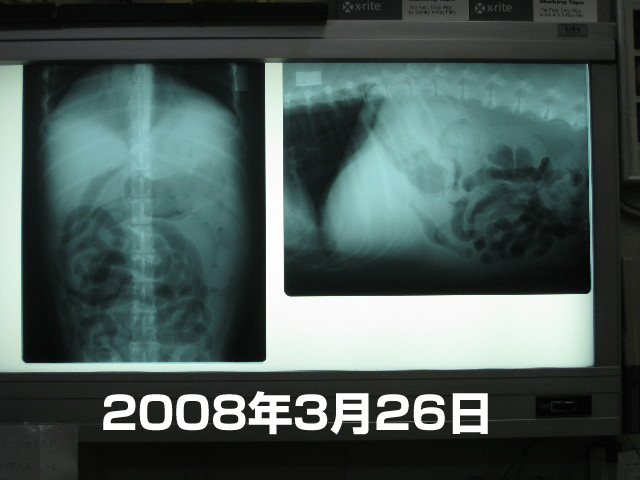

●ハアハアが気になるし、おなかがあいかわらずぽっこりしているのも気になるし、ママはおなかに何かあるのでは?という気がするのでレントゲンもとってもらった。

腸にはガスがいっぱい。(黒く見えるのは空気=ガス)

ハアハアいっているので空気を飲み込んでしまって、こんなに腸にガスがたまっちゃうのかな。

(画像だとみにくいけど)肺は10日前のと比べると血管が動いているというか少しあやしい感じ(ベベはフィラリアをしているので前から以前から肺の繊維化は多少ある)

黒く写っている所が肺。